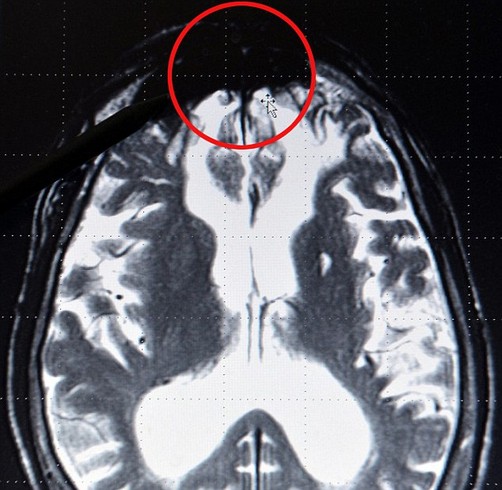

Según sus conclusiones âtodavía provisionales, como todo en la cienciaâ esta manifestación del mal podría originarse en un “mancha” que se ubica en el lóbulo central y que, asegura el científico, comparten los cerebros de estas personas.

Lo sorprendente, sin embargo, fue que al tomar radiografías del cerebro de los criminales, en casi todos ellos puede observarse una masa oscura en la región central, la cual sugiere, según Roth, que existe una predisposición genética a la violencia, aunque igualmente influyen factores de neuroquímica (en particular relacionados con la segregación de serotonina). En cualquier caso, dice el investigador, “esta es definitivamente la región del cerebro donde el mal se forma y donde este se esconde”.